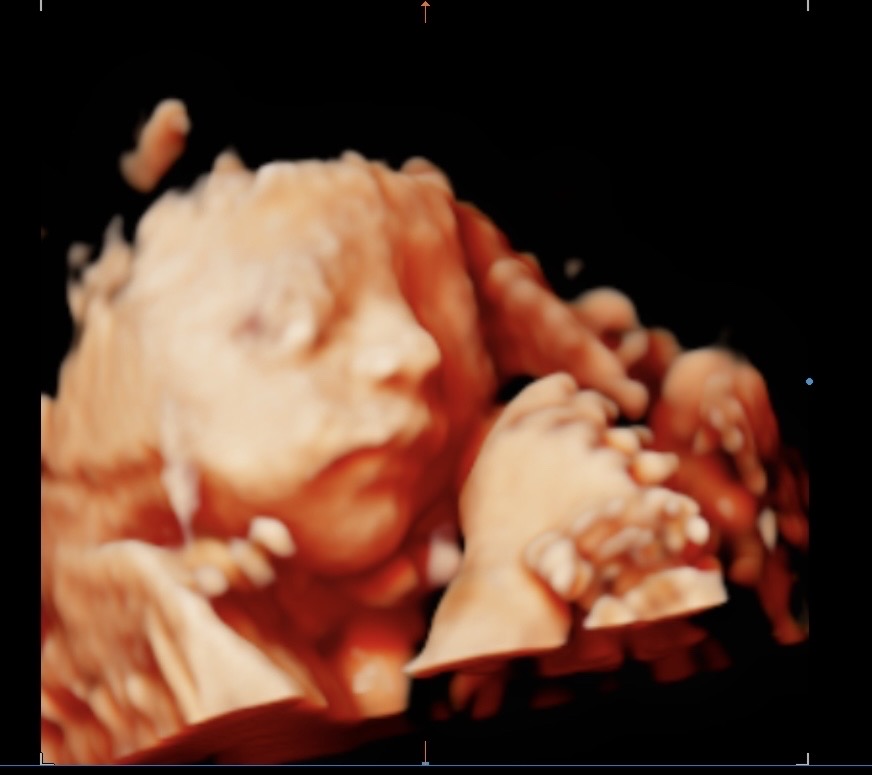

27주차 아기 초음파

너무 귀여워요....... 초음파랑 실물이랑 비슷하게 나오나요? 너무궁금하고 귀엽고 얼굴 자세히 처음으로 보니깐 더 애정생기고 도치맘 예약이네요.. 참고로 아들입니다

초음파랑 똑같이 나와요 ㅋㅋㅋ 애기 너무 예쁘네요😍